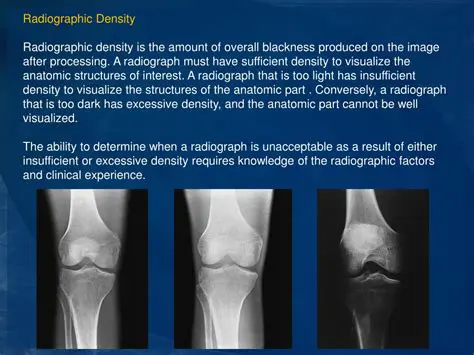

The Importance of Radiographic Image Sharpness